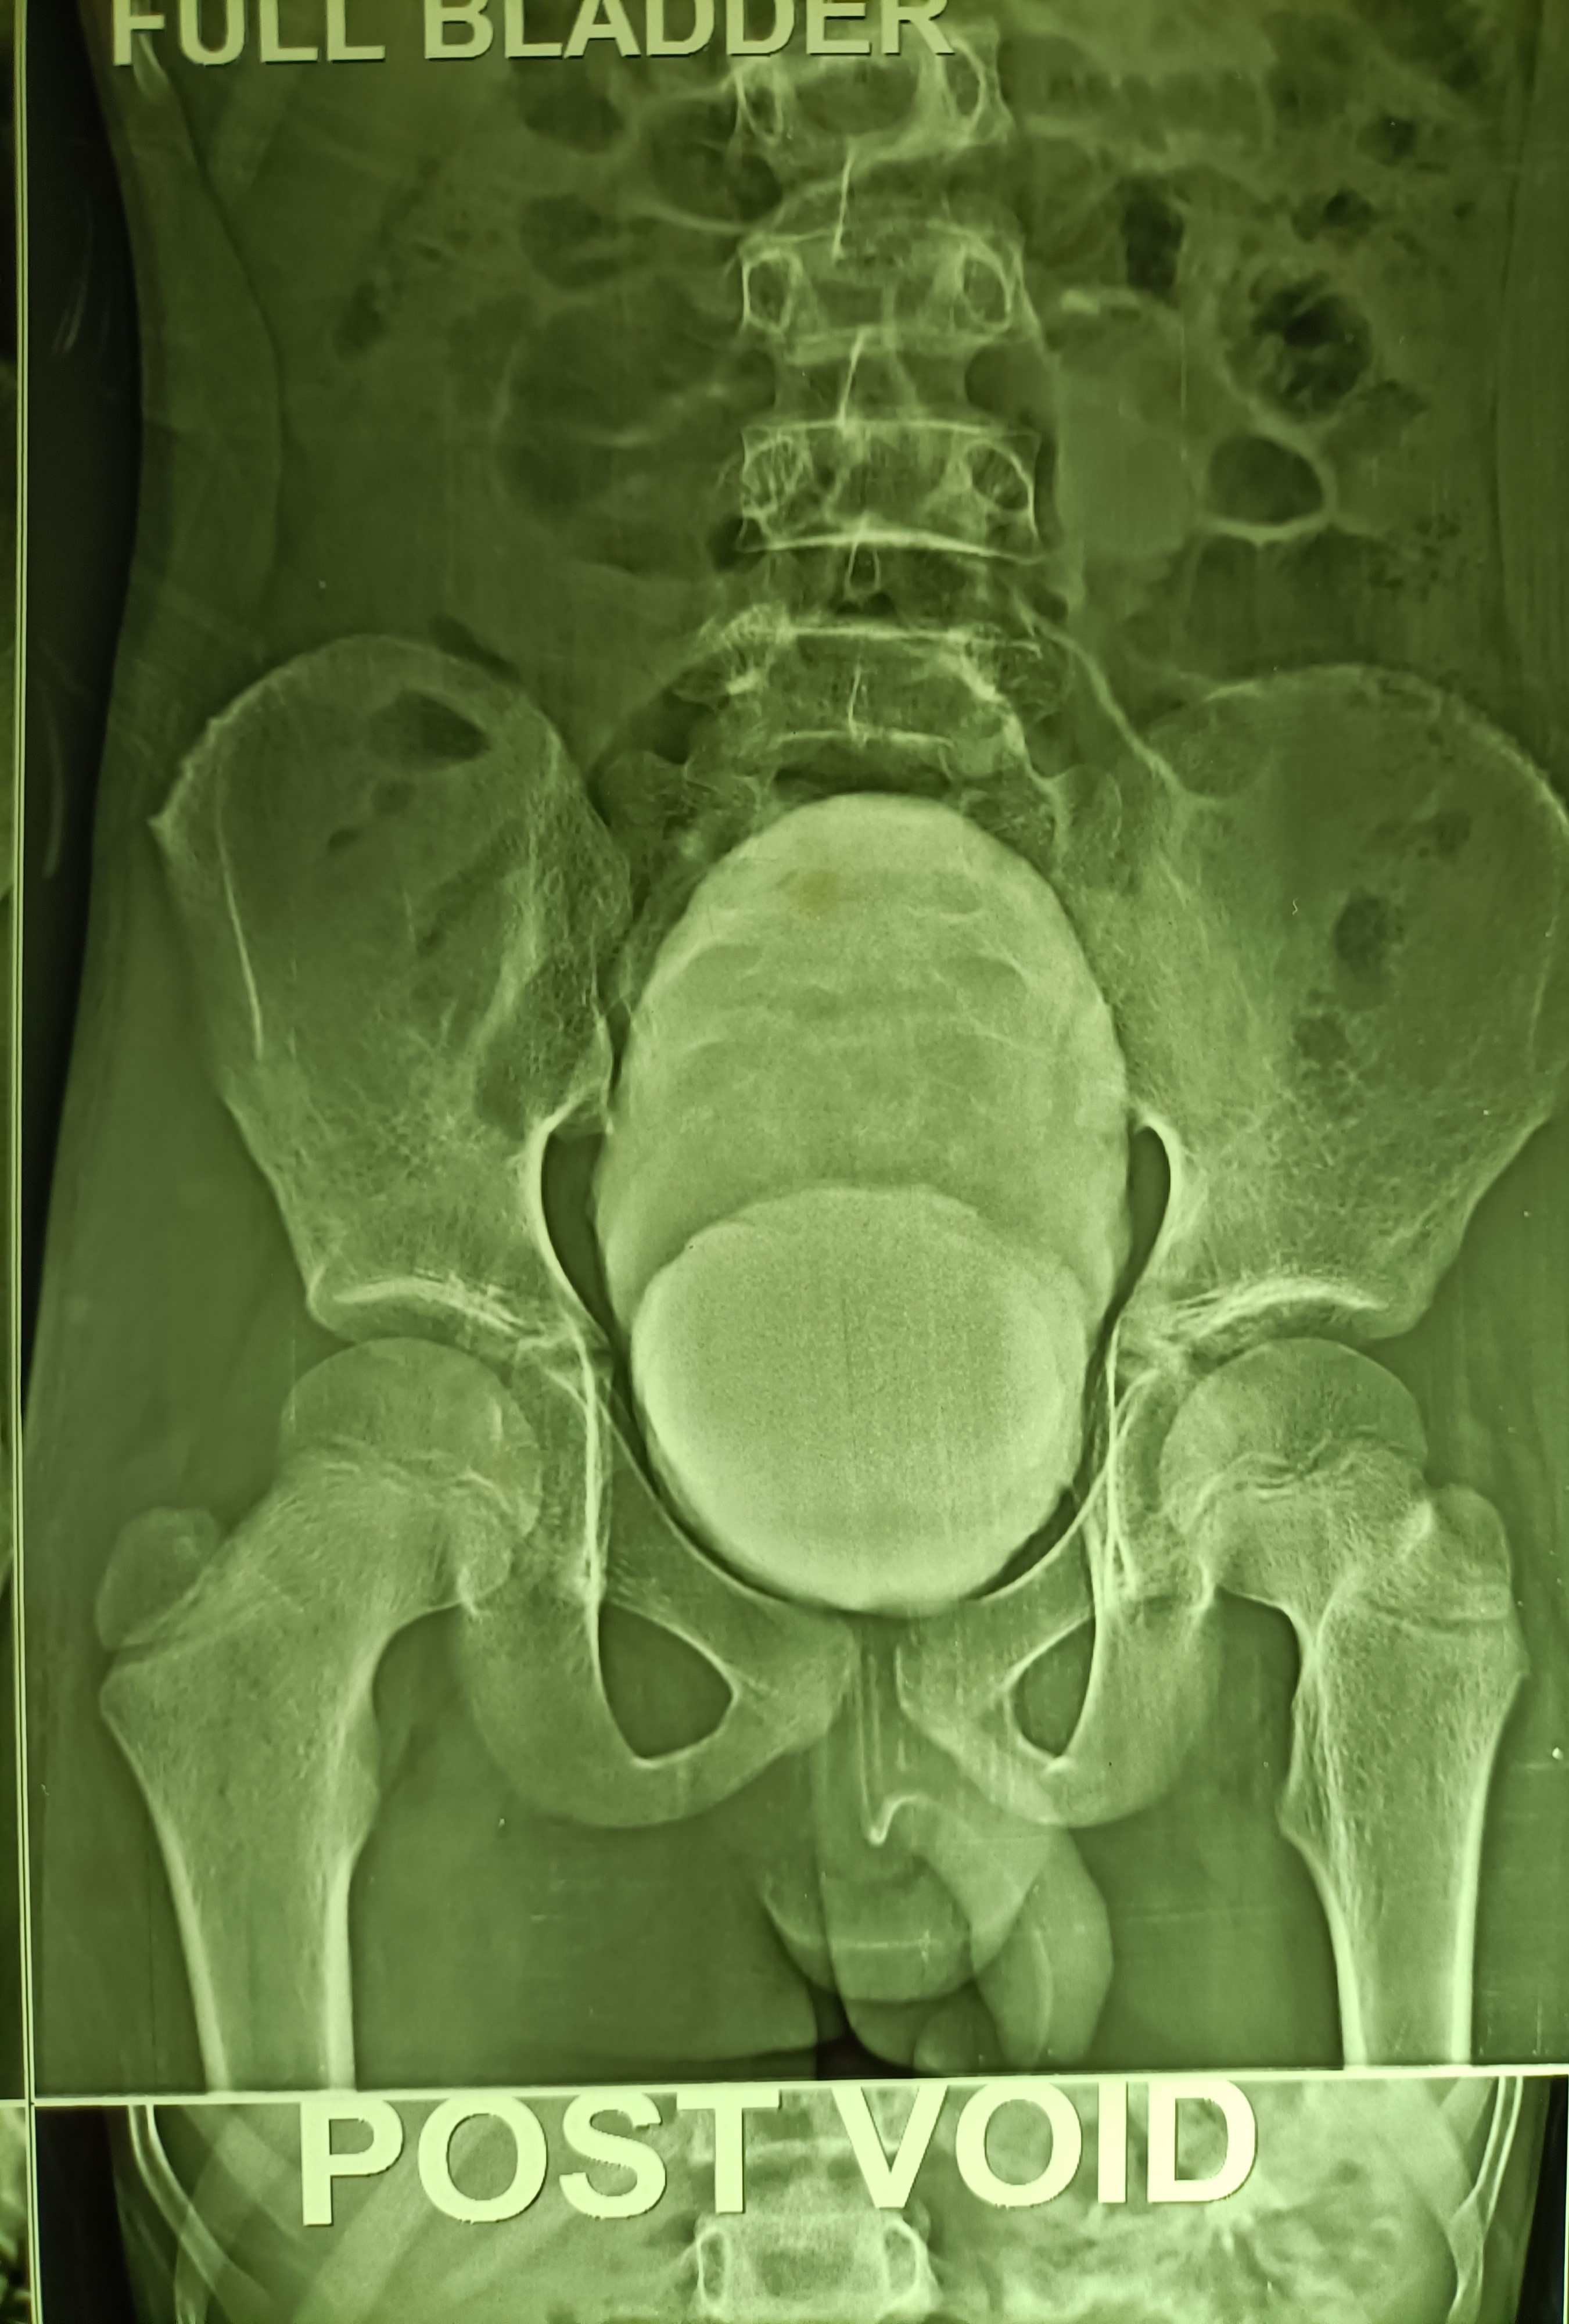

A 13 years old boy presented with acute painful retention of urine at night (it was actually an acute-on-chronic retention, as it came to light later) and since catheterization could not be done due to the tightly stenosed preputial opening, the bladder was emptied with a suprapubic needle. An ultrasound scan in the morning reported circumferential wall thickening of the urinary bladder and a V-shaped deformity of the bladder neck, suggesting a diagnosis of posterior urethral valves.

Paediatric surgical consultation was obtained and an MCU was suggested. This was done and suggested a diagnosis of neurogenic bladder while ruling out posterior urethral valves.

A routine circumcision was performed the same day and the child remains well thereafter.